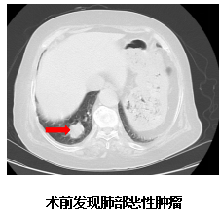

检查结果揭示了她病情急转直下的原因:头部MRI显示右侧额叶运动前区皮层转移灶,伴有明显脑水肿,严重压迫运动功能区。更复杂的是,胸部CT发现了右肺占位病变。高龄、病情进展迅速、肺部原发病变,使这个病例充满挑战。